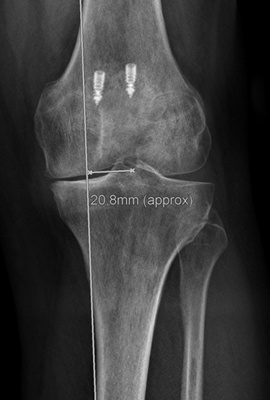

Dr. med. Alexander Strehl: Bei einer Umstellungsosteotomie wird die Lastachse im Knie und somit auch auf den Knorpel korrigiert. Korrekterweise geht die Belastung vom Oberschenkelkopfzentrum zum Sprunggelenkszentrum etwa mittig durchs Knie. Bei O- oder X-Beinen weicht diese Achse ab. Dies kann aus unterschiedlichen Gründen sein, zum Beispiel durch einen früheren Beinbruch oder weil der Patient in der Zeit des Skelettwachstums viel Fussball gespielt hat, kommt aber auch oft ohne eigentliche Ursache vor. Das O-Bein ist häufiger als das X-Bein. Manchmal sieht man diese Abweichung der Beinachse nicht auf den ersten Blick, sondern erst mit einer Ganzbeinstandaufnahme.

Durch O- oder X-Beine wird der Knorpel im Knie einseitig belastet. Da reichen manchmal schon wenige Millimeter, die die Achse abweicht. Folge ist, dass sich eine Knorpelseite deutlich schneller abnutzt als die andere. Mit der Operation wird die Belastung zurück auf die Mitte gesetzt oder eine kleine Überkorrektur auf die gesunde Seite vollzogen, sodass diese etwas mehr belastet und die abgenutztere Seite entlastet wird.